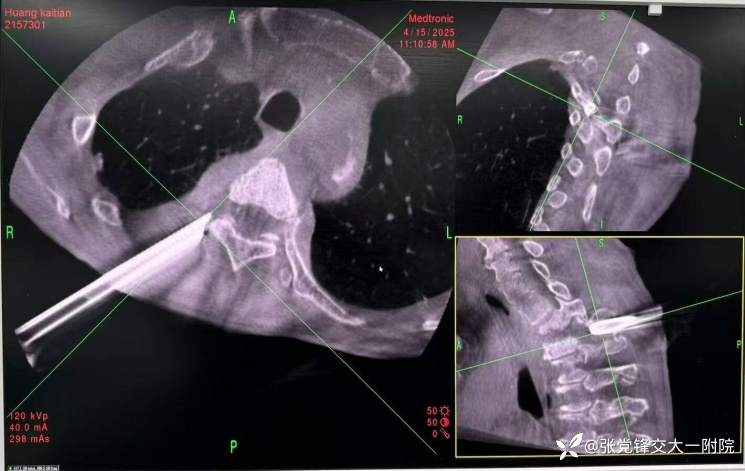

术前CT

3.在导航引导下确定右侧穿刺点,选择侧后方肋横突间隙入路,避开肋骨头、穿刺点位于胸2棘突右侧旁开 3-4cm位置, 沿穿刺点切开皮肤 1cm, 导航实时引导下以 20G细针穿刺至胸2-3椎间隙右后外侧缘方向,导航三维显示在矢状位、横断位、冠状位上穿刺针位置良好,避免偏外损伤胸膜或偏内进入椎管损伤神经,导航引导沿穿刺针置入工作通道,过程中轻柔分离软组织,避免损伤神经血管束,避免穿透胸膜,连接椎间孔镜系统,生理盐水持续灌注。导航引导下沿正确方向逐渐将工作通道旋转打入胸2-3椎间隙后外侧缘,清除通道内此过程扩张脱落的少量骨性组织,进入病变区域,可见椎间隙后方有干酪样坏死物、死骨及炎性组织,使用镜下血咬骨钳等清除这些病变组织,扩大减压至相邻椎体后缘,病变组织清除后可见椎间隙后方脊髓硬膜囊膨起,神经根显露,脊髓和神经根压迫明显解除,并可见首髓波动。